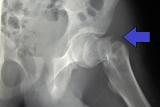

Согласно исследованию, опубликованному Journal of the American Academy of Orthopaedic Surgeons, у людей, переживших перелом бедра, в первый год наблюдается заметное ухудшение функции и самочувствия...

09.02.2021